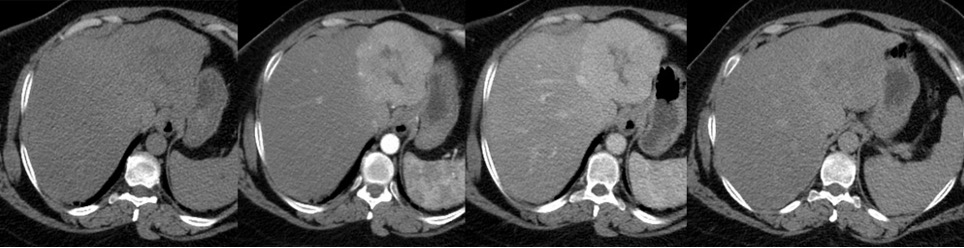

Aspetto TC

- Formazione isodensa, dotata di precoce enhancement arterioso con isodensità in fase tardiva.

- Le lesioni di grandi dimensioni possono essere eterogenee, con fenomeni necrotico-emorragici intralesionali.